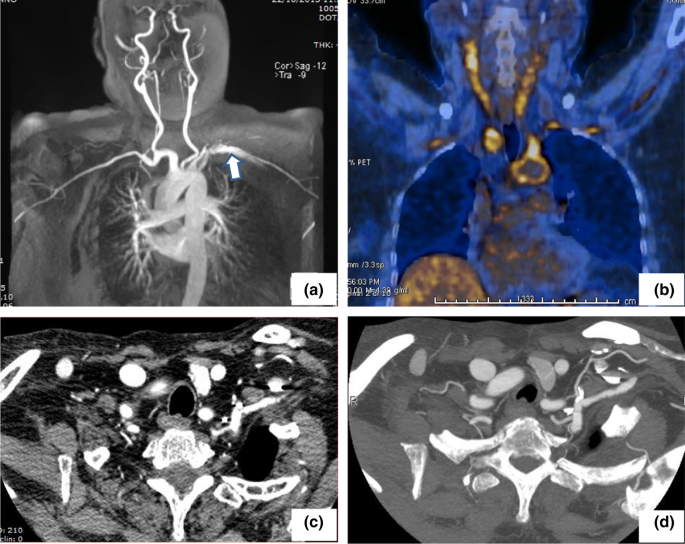

18F-Fluorodeoxyglucose positron emission tomography/computed tomography (FDG-PET/CT) is being used with increasing frequency due to its high sensitivity and the ability to detect the sites, extent, and severity of vessel inflammation. Within our cohort, this angiographic tool was employed in 12 patients (27.9%) at diagnosis and provided clear images of high sensitivity (Fig. 5). However, the limitations of FDG-PET/CT include a rapid decrease in sensitivity in patients treated with GC for 1–2 weeks prior to the examination, high-level radiation exposure, and the possible misinterpretation of the lesions as atherosclerosis [33, 34].

Fig. 5

figure 5

18F-FDG PET/CT in a 42-year-old female patient with type V Takayasu arteritis who complained of fatigue, weight loss, fever, and severe headache. Maximum intensity projection (MIP) (a) and axial fused images showed increased 18F-FDG uptake (yellow arrows) in the aorta and its main branches, particularly in carotid (b) and subclavian (c) arteries and in the distal abdominal aortic wall (d). After 6 months of therapy, follow-up PET/CT images show clearly decreased uptake in the large arteries (E–H)

Magnetic resonance angiography (MRA), performed in 9 of our patients (20.9%), provided detailed images of the vascular tree (Fig. 6). The further advantages of MRA include reliable information on luminal and mural changes, the examination of vessels in any suitable plane, the option to obtain serial assessments over time given the lack of exposure to ionizing radiation (a particularly valuable feature in young patients), and the short time required for image generation. The disadvantages include difficulty in visualizing small branch vessels and vessel wall calcifications, and the high cost of the technique [35, 36].

Fig. 6

figure 6

a Angio-MR with intravenous paramagnetic contrast medium shows a moderate ectasia and an irregular contour of the proximal tract of left subclavian artery (arrow). b By 18FDG-PET/CT an increased uptake of the radiopharmaceutical can be seen at the level of the neck vessels and thoracic aorta. c Following therapy, CT with intravenous iodinated contrast medium reveals a reduced irregularity of the left subclavian wall and a more homogeneous gauge. d The same CT with maximum intensity projection (MIP) algorithm

Clinical and imaging-based evaluations often show a variable correlation with the disease course [37]. In the assessment of TAK, MRA and FDG-PET/CT often provide unique and complementary information. Although MRA is more suitable to establish the extent of the disease, FDG-PET/CT is preferred if the goal is to assess vascular activity.